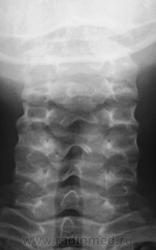

Ниже привожу рентгенограммы детей за вчерашний и сегодняшний день.

Первая рентгенограмма в положении сгибания - таже клиновидность щели, остальные рентгенограммы в срединном положении головы. Все рентгенограммы разных детей.

https://www.instagram.com/pediatricradiology/